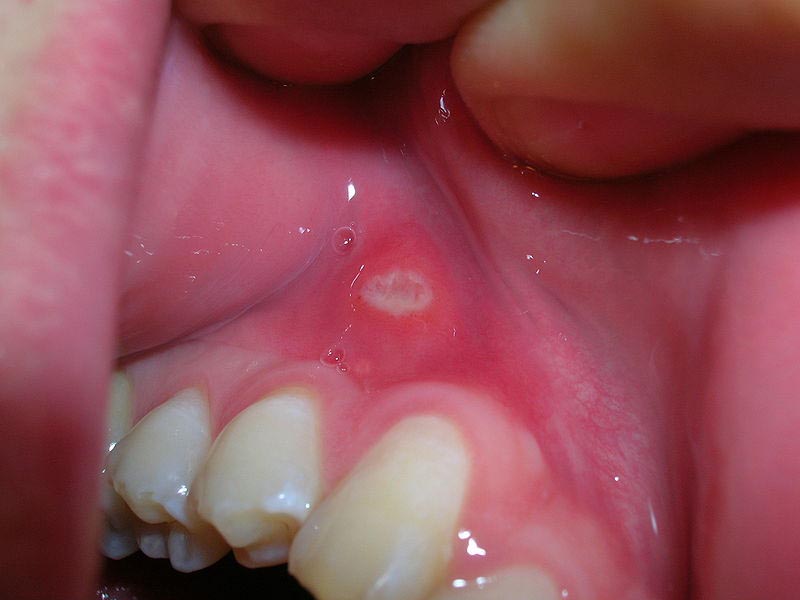

Afte, koje se često nazivaju i aftozni ulkusi, zapravo su male, plitke ranice koje se javljaju na sluznici usta. Najčešće se pojavljuju unutar usana, na jeziku, desnima ili nepcu. Iako ne predstavljaju ozbiljnu opasnost za zdravlje i ne ostavljaju dugoročne posljedice, mogu biti vrlo neugodne zbog bola koji izazivaju. Ovaj bol često otežava svakodnevne aktivnosti, kao što su govor, konzumacija hrane ili čak žvakanje. Važno je naglasiti da afte nisu zarazne, što znači da se ne mogu prenijeti s osobe na osobu, a razlikuju se od herpesnih promjena koje nastaju kao posljedica virusne infekcije.

• Afte obično počinju kao sitne bijele ili žućkaste ranice okružene crvenim rubom. Iako najčešće ostaju malih dimenzija, ponekad mogu narasti i do nekoliko centimetara, što dodatno pojačava bol. Prema dostupnim informacijama, njihova pojava najčešća je na unutrašnjoj strani usana, na jeziku, desnima i ispod jezika. U većini slučajeva, obične afte prolaze spontano u roku od sedam dana, bez potrebe za posebnim tretmanom. Međutim, postoje i teže forme koje mogu trajati duže i ostavljati jači osjećaj nelagode.

Simptomi afti uključuju pojavu jedne ili više bolnih ranica koje su najčešće bijele, žute ili sivkaste boje, okružene crvenilom. Prije nego što se pojave, mnogi primjećuju osjećaj peckanja ili žarenja na određenom dijelu sluznice. U težim slučajevima, kod nekih osoba mogu se javiti i drugi simptomi poput povišene temperature, umora ili uvećanih limfnih čvorova. Iako afte najčešće prolaze same od sebe, postoje načini da se bol ublaži i da proces zacjeljivanja bude brži.